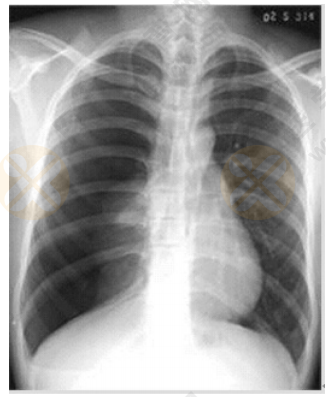

根据下图所给X线片分析临床意义。(5分)